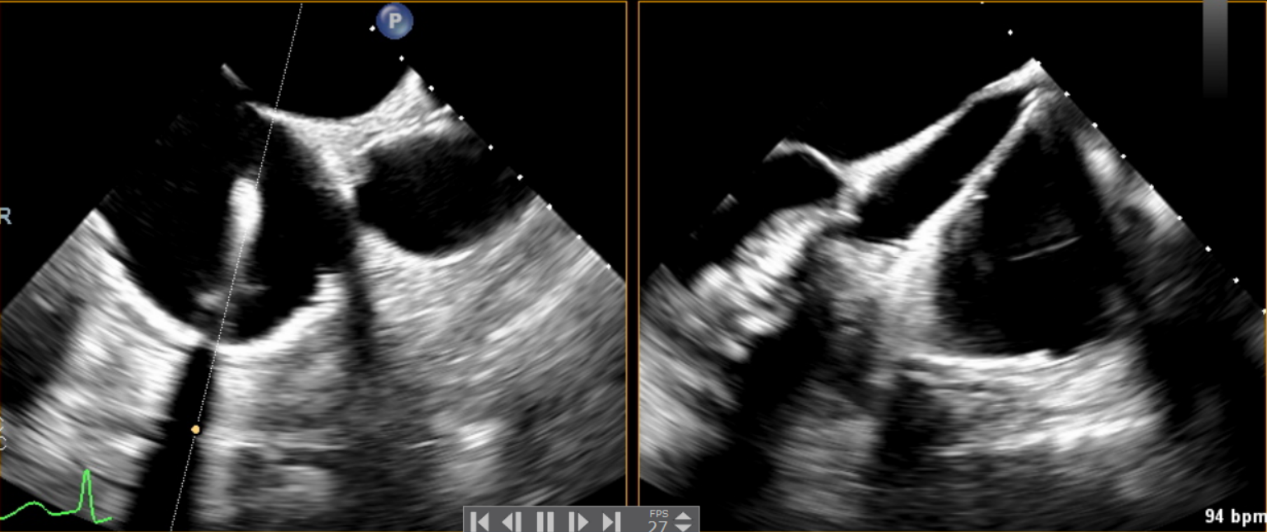

近日,美國紐約Montefiore醫(yī)學中心(Montrefiore Medical Center)的Azeem Latib教授團隊成功應(yīng)用LuX-Valve Plus經(jīng)血管三尖瓣置換系統(tǒng)為兩位三尖瓣大量反流的患者完成三尖瓣置換手術(shù)。術(shù)后超聲顯示人工三尖瓣植入穩(wěn)定,瓣葉啟閉良好,僅殘余微量瓣周漏?;颊哂谑中g(shù)室即刻拔除氣管插管,血流動力學改善顯著。此次手術(shù)是LuX-Valve Plus于紐約的首次臨床應(yīng)用,治療效果優(yōu)異。

術(shù)后Azeem Latib教授對LuX-Valve Plus經(jīng)血管三尖瓣置換系統(tǒng)的器械性能和治療效果大為稱贊,并且認為LuX-Valve Plus的手術(shù)體驗非常好。從治療效果來看,術(shù)后即刻超聲顯示三尖瓣反流幾乎完全消失,血流動力學改善顯著,患者恢復(fù)快。在面對復(fù)雜解剖結(jié)構(gòu)、超聲影像質(zhì)量不佳、有起搏導(dǎo)線干擾時,Lux-Valve Plus也體現(xiàn)了極強的適應(yīng)性。Thomas Modine教授參與了術(shù)中指導(dǎo),他同樣再次肯定了LuX-Valve Plus術(shù)中操作的便捷性,認為LuX-Valve Plus容錯率高,對術(shù)中影像的依賴小,并表達了后期希望可以更多地應(yīng)用LuX-Valve Plus三尖瓣置換系統(tǒng)于臨床實踐,讓更多的三尖瓣重度反流患者盡早獲益,改善預(yù)后。

LuX-Valve Plus采用經(jīng)頸靜脈入路,不僅對患者損傷進一步減小,同時為術(shù)者提供了便捷的術(shù)中操作方式。與一代產(chǎn)品LuX-Valve共同已經(jīng)為全球數(shù)百名患者提供了有效的治療,最長隨訪時間逾四年,長期安全性和有效性得到充分驗證。